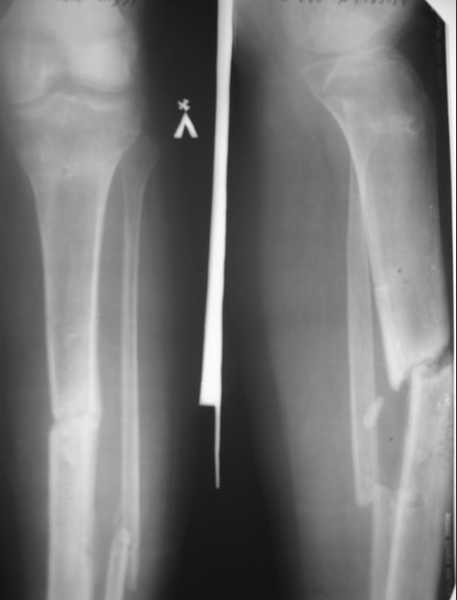

Здравствуйте,уважаемые коллеги. Хотелось бы услышать ваше мнение по следующему случаю: пациент 20 лет, травма в июне 2007 г. Открытый перелом костей левой голени со смещением отломков. В этот же день выполнена ПХО открытого перелома костей левой голени, фиксация в КДА по Илизарову. Раны заживали вторичным натяжением. В январе 2008г. сняли аппарат, по причине нестабильности, - гипсовая иммобилизация. На данный момент согласно контрольным рентгенограммам и времени прошедшего с момента травмы имеется нормо, гипотрофичный ложный сустав большеберцовой кости. Местно - признаков воспаления не определяется. Лабораторные показатели в пределах нормы.Планирую: 1. Рассверлить канал риммерами до диметра 12 – 13 мм, и выполнить остеосинтез блокированным канюлированным стержнем диметром 11 – 12 мм. Вопросы:1. Достаточно ли для стимуляции остеогенеза только рассверливания костно – мозгового канала, есть ли необходимость в костной пластике и декортикации, нужно ли выполнить остеотомию малоберцовой кости?2. Есть ли необходимость первичной динамизации, или сначала в статику, потом динамизация? Если в статическом блокировании, то через сколько необходимо выполнить динамизацию?3. Когда разрешить нагрузки на конечность? Что вы посоветуете? Где могут быть - технические трудности. С уважением Д. Магданов.

На Вашем месте я бы сначала наложил спицестержневой аппарат, выполнил остеотомию малоберцовой кости. После операции устранил бы имеющееся смещение (оно существенное - имеется укорочение, смещение по ширине и угловое смещение). И лишь потом, через несколько дней, выполнил бы интрамедуллярный остеосинтез.

Объясню свою позицию. При рассверливании проксимального отломка риммер будет идти по задней стенке канала и упрется в кортикальный слой дистального отломка, или же, что еще хуже, выйдет за пределы кости. Это может усложнить ход операции. Одномоментно репозицию будет выполнить трудновато. Это обусловит травму мягких тканей в области перелома. Вполне возможно, что кожа в данной зоне рубцово изменена и припаяна к большеберцовой кости. При одномоментном устранении смещения ее можно повредить.

Денис, интересно было бы посмотреть рентгенограммы в аппарате Илизарова. Интересно, почему через полгода фиксации в аппарате имеется такое положение отломков. Спрашиваю не из вредности. Просто в соответствии с предлагаемым мной планом потребуется сделать то, что пока за время лечения не было сделано.

Денис, по представленным снимкам могу осторожно предположить, что Вы не относитесь к лагерю "аппаратчиков" (меня-то, наоборот, так коллеги на работе обзывают). Отдаю себе отчет, что предложенный мной вариант лечения покажется изящным не каждому травматологу.